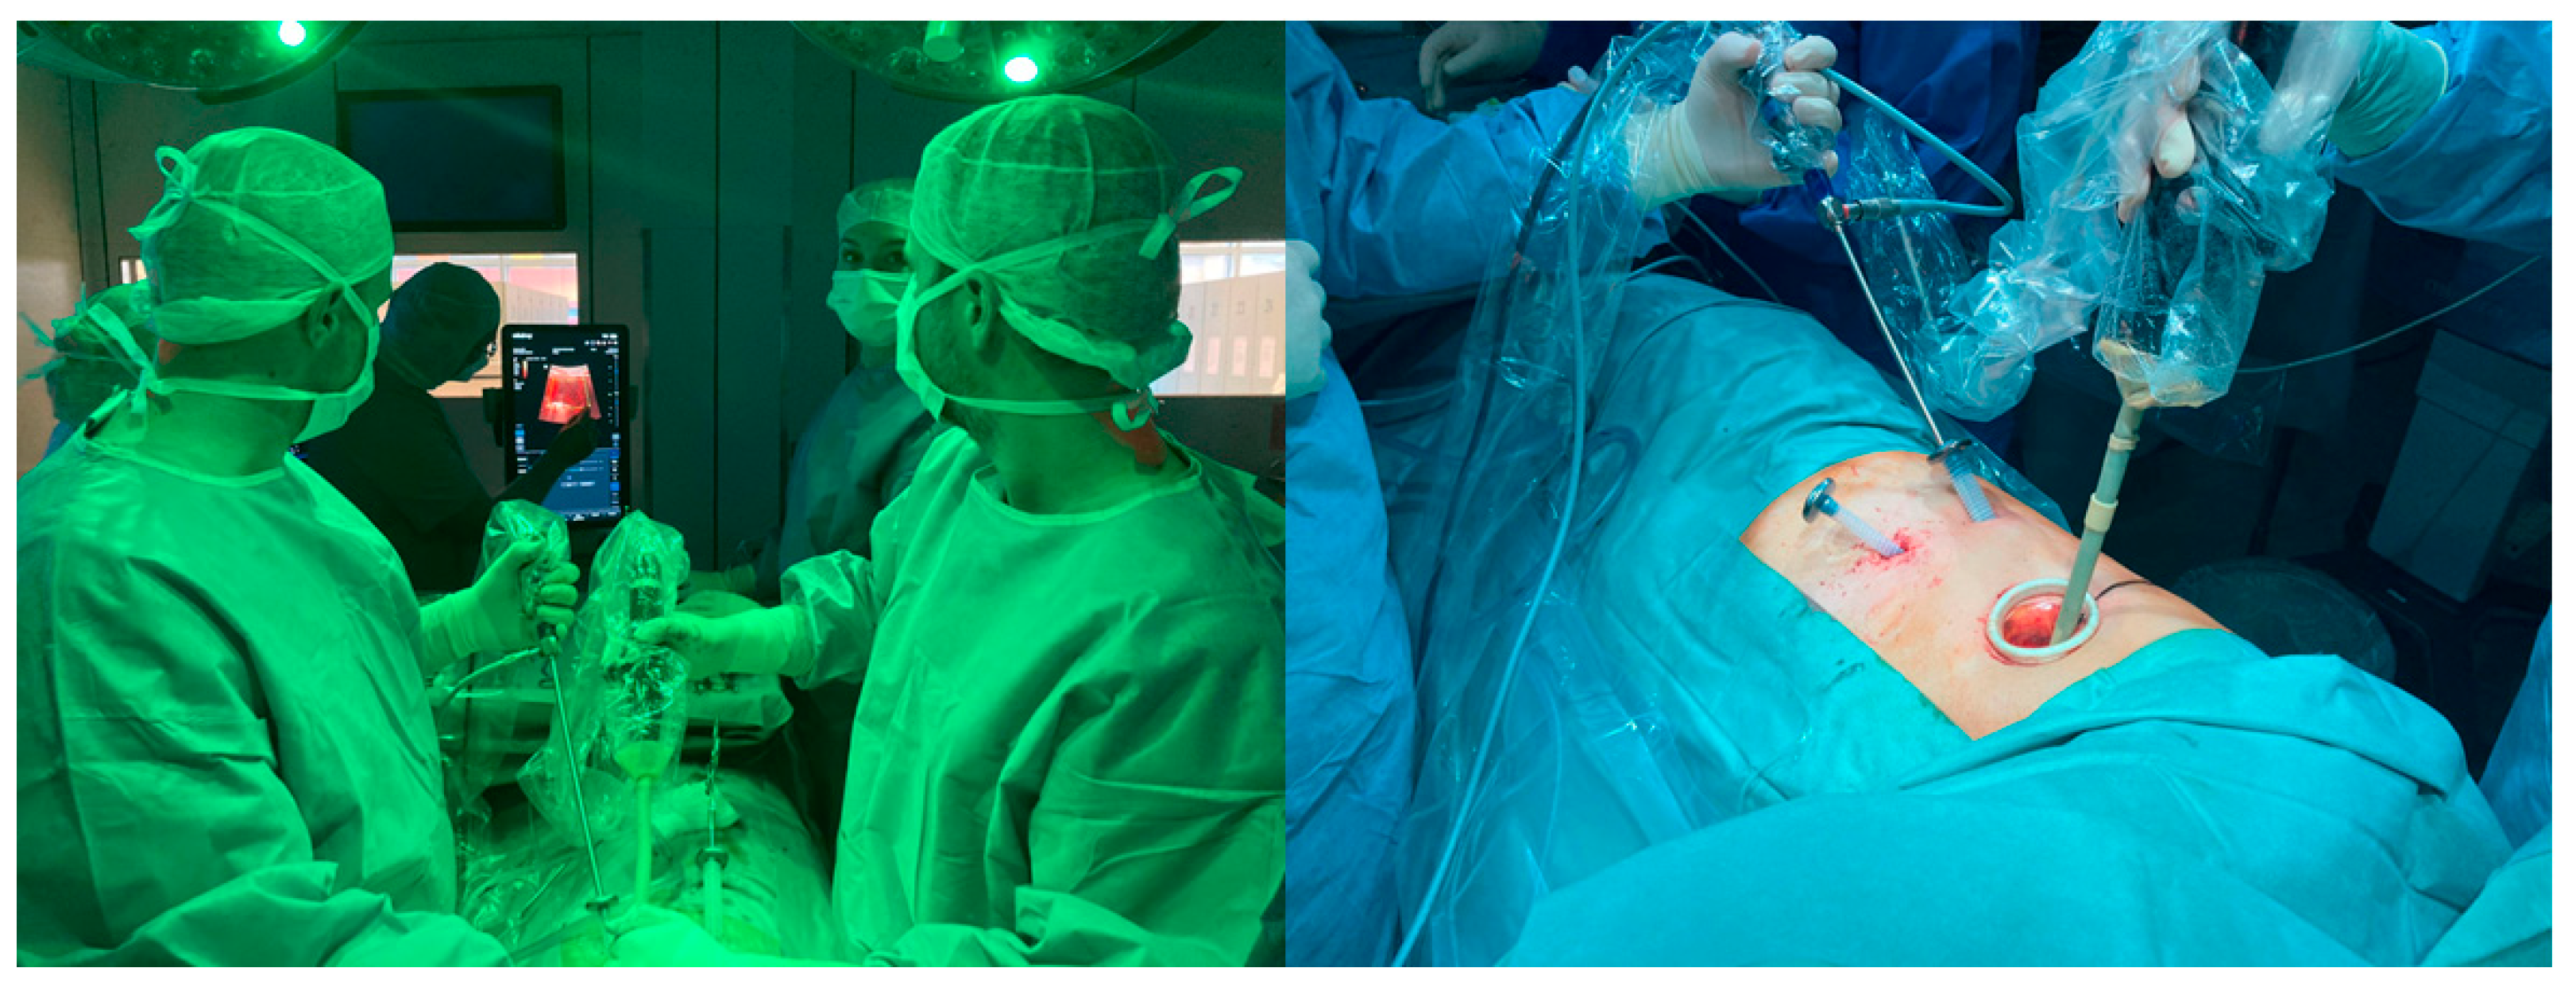

2.3. Intraoperative Approach for Io-CEUS